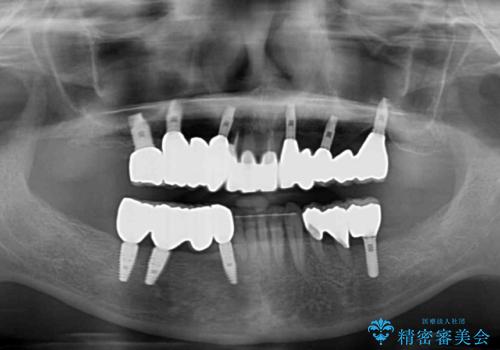

- 歯周病を放置したことで奥歯が抜け、前歯も痛くなってきたとのことで来院された患者様です。

奥歯はほとんどを抜歯しなければならない状態であり、抜歯をせずに済む歯も歯周外科処置や矯正治療を行う必要がある状態でした。

歯を抜かないといけない部分はインプラントとオールセラミッククラウンにより咬合を回復させ、歯周外科処置を行う歯については、同じくオールセラミッククラウンにて補綴治療を行うこととしました。

外科処置を多く行ったため、その待ち時間が長くかかり、さらには途中矯正治療も行なったので、治療期間は長期間となりました。